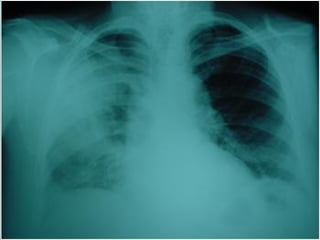

Tuberculosis pulmonar

Calcificaciones tras TBC   Caverna TBC   TBC miliar

primaria

Tuberculosis pulmonar Calcificaciones trasTBC Caverna TBC TBC miliar primaria